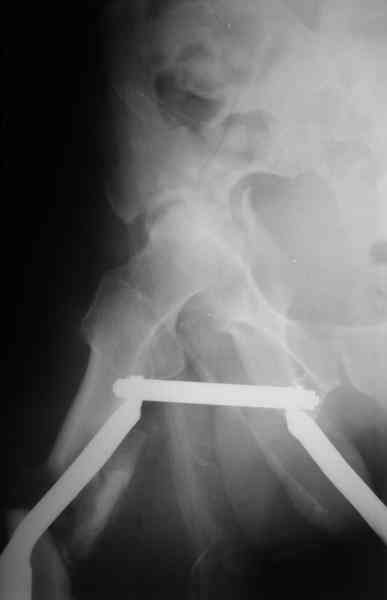

Отправитель: Maxim Agalakov 26 Июль 2006, 21:59

Здравствуйте Анатолий Федорович. Сегодня заситезировали этопу пациенту длинные трубчатые кости. В отношении вертлуги мы остановились на остеосинтезе вертлужной впадины из доступа Кохер -Лангенбек. Необходимость (и возможность) закрытого вправленя через месяц представляется сомнительной - даже если удастся - судьбу головки

это вряд ли изменит в лучшую сторону, а если вправить, то на нее будет осуществляться давление отломком,связанным с осевым скелетом. В дальнейшем, если возникнут ожидаемые проблемы с АНГБ, коксартрозом, вернямся к этому больному. (описанную вами операцию надо хоть посмотреть разок, наверняка есть какие-нибудь тонкости).